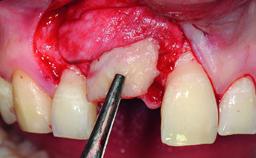

Replacement of an Ankylosed Upper Left Central Incisor: Bone Augmentation and Socket Grafting, Late Placement of an RC Bone Level Implant

Bone Augmentation Horizontal|Simultaneous|Staged

Augmentation Materials Autogenous chips|Xenogenous